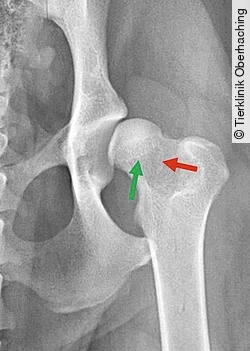

Im Verlauf des letzten Jahrzehnts wurden zusätzliche röntgenologische Merkmale untersucht, die von klinischer Signifikanz sein sollen [61], [62], [63], [64] ([Abb. 3]):

- die Morganlinie (Caudolateral Curvilinear Osteophyte, CCO)

- die Kragenlinie (Circumferential Femoral Head Osteophyte, CFHO)

- die sogenannte „Puppy Line“ im Bereich des Femurhalses

Die Puppy Line scheint nicht mit der Entstehung degenerativer Gelenkveränderungen assoziiert zu sein. Weiterhin verschwindet sie im Alter von ca. 18 Monaten [65].